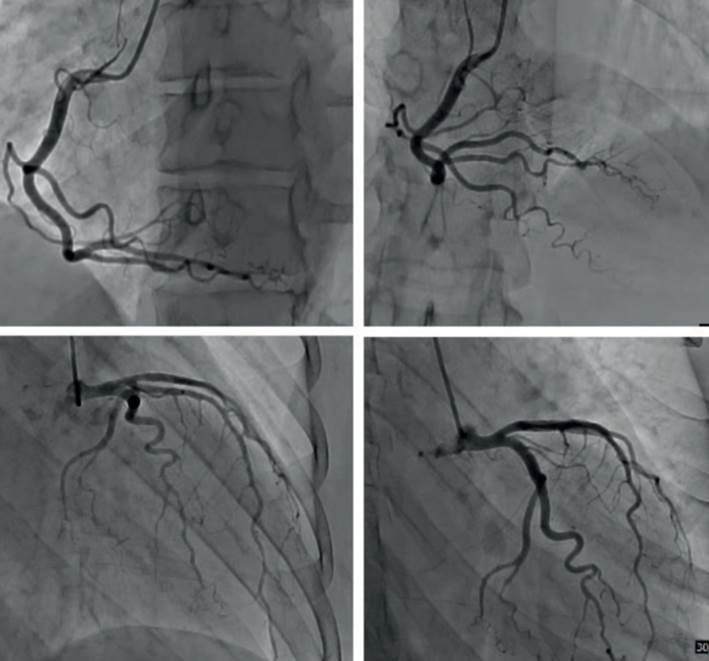

Se realizó cineangiocoronariografía (CACG) que mostró arterias coronarias epicárdicas sin lesiones angiográficamente significativas (figura 3).

La miocarditis lúpica se ha reportado en 3-9% de los pacientes con LES. La edad media de presentación es de 30 años y suele diagnosticarse al inicio de la enfermedad. La presentación puede variar desde pacientes clínicamente asintomáticos hasta shock cardiogénico. Las manifestaciones más frecuentes son dolor torácico, arritmias y síntomas de insuficiencia cardíaca. Se asocia con un elevado nivel de actividad de la enfermedad, en la gran mayoría de los pacientes (97%) se acompaña con el compromiso de otros órganos3. En pacientes en los que predomina el dolor torácico como forma de presentación, como en nuestro caso, es necesario descartar el compromiso coronario.